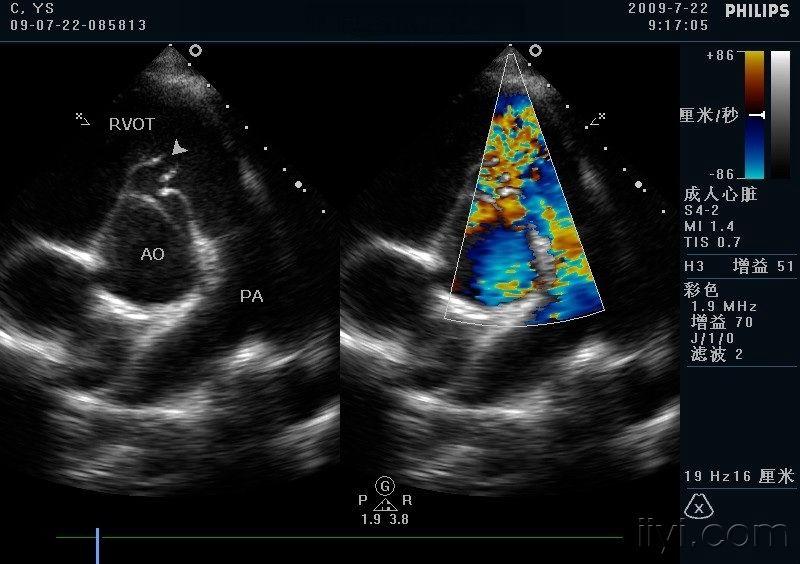

室间隔缺损 主动脉右冠窦瘤破入右室流出道